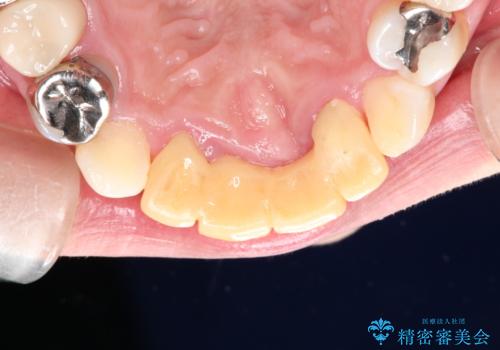

3年間仮歯 前歯セラミックブリッジ

- 3年間仮歯のまま過ごしていたそうです。 色の変色と臭いが気になり来院されました。

- 61万6千円 (根管10万x1本 コア1万x1本 仮歯1万x4本 セラミック(スタンダード)10万x4本)費用は治療当時の料金となります